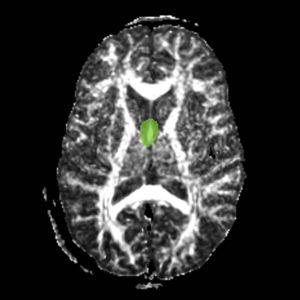

Fornix

The ROI1 was drawn on the sagittal slice, 5 slices superior to the anterior commisure (Fig. 8 & 10). The ROI2 was drawn on a coronal slice where the crux of the fornix was present. It was not always the same slice for both sides (Fig. 9 & 11).

Figure 8. Axial View of ROI 1

Figure 9. Coronal View of ROI 2 (left=11, right=13)

Figure 10. Sagittal View of Fornix, ROI 1 (both left and right)

Figure 11. Sagittal View of Fornix, ROI 2 (right)

The color coding of the resulting ROIs is as follows:

ROI 1: Left & Right (16)

ROI 2: Left(5) - Right(15)